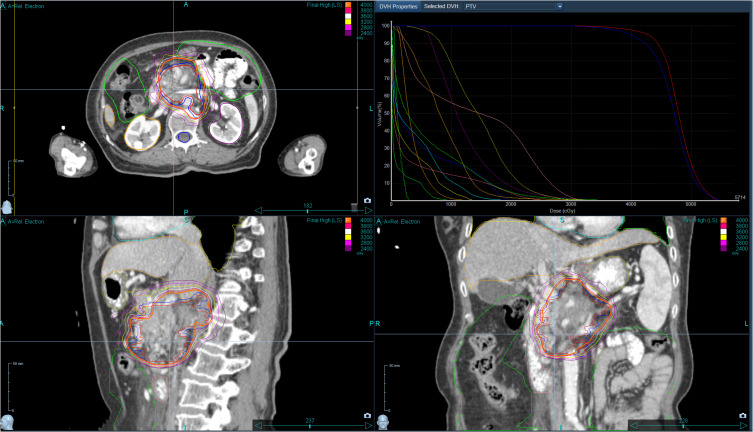

Objective: This study aimed to investigate the effectiveness and safety of CyberKnife in the treatment of primary pancreatic cancer with metastases to the gastrointestinal tract (ie, primary pancreatic adenocarcinoma metastasizing to gastrointestinal organs).

Methods: A total of 106 patients with primary pancreatic cancer and metastases to the gastrointestinal tract admitted to our hospital received CyberKnife treatment. Recent treatment efficacy (assessed at 3 months post-treatment), median survival period, pain levels, and adverse reactions were analyzed.